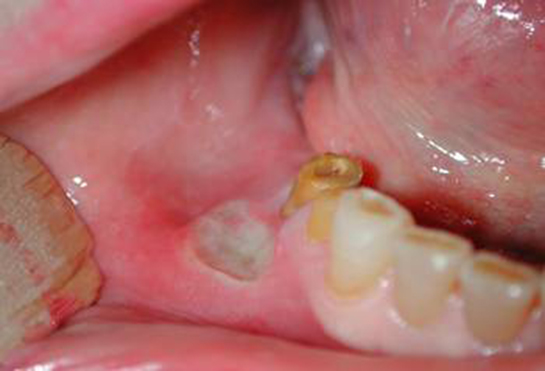

Üst damak şişmesi, ağız ve diş sağlığı ile ilgili önemli bir durumdur. Bu durumun birçok nedeni olabilir ve genellikle ağız içindeki bir iltihaplanma, enfeksiyon veya diğer sağlık sorunları ile ilişkilidir. Bu makalede, üst damak şişmesinin olası sebeplerini detaylı bir şekilde inceleyeceğiz. 1. Diş Enfeksiyonları Diş enfeksiyonları, diş köklerindeki bakteriyel enfeksiyonlar nedeniyle meydana gelir. Bu tür enfeksiyonlar, dişin çevresindeki dokulara yayılabilir ve üst damakta şişmeye neden olabilir. Diş absesi, genellikle yoğun bir ağrı ile birlikte gelir ve acil tedavi gerektirir.

3. Viral ve Bakteriyel Enfeksiyonlar Viral veya bakteriyel enfeksiyonlar, üst damak şişmesine yol açabilecek diğer yaygın nedenlerdir. Özellikle herpes simplex virüsü, ağız içinde yaralara ve şişmelere neden olabilir. Bakteriyel enfeksiyonlar da benzer şekilde, damak bölgesinde iltihaplanma yaratabilir.

Enfeksiyonlar da bir diğer olası sebep. Ağız içindeki bakteriyel veya viral enfeksiyonlar, iltihaplanmaya ve şişmeye neden olabilir. Ayrıca, dil yaraları veya soğuk algınlığı gibi rahatsızlıklar da damağınızda şişlik yapabilir.